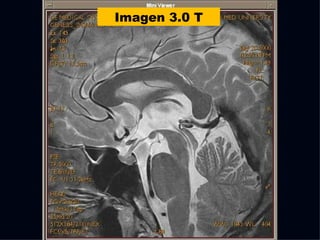

The document discusses the contributions of various figures in the field of medical imaging, including Wilhelm Röntgen and his discovery of X-rays, and the development of CT imaging and MRI technology. It highlights the historical significance of early imaging techniques and the initial skepticism from medical professionals regarding their usefulness. Key milestones in imaging are noted, along with the eventual acceptance of such technologies in clinical practice.